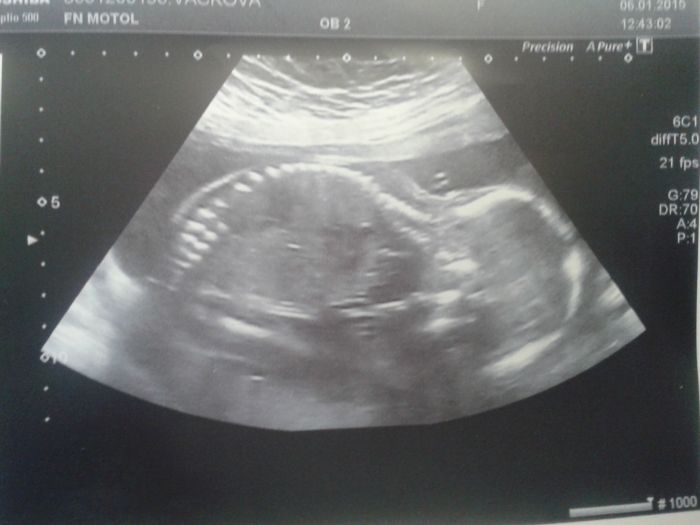

Mimčo na UTZ nechtělo zrovna moc pozovat